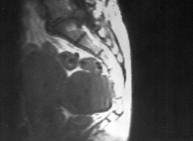

An ultrasound (abdominal or transvaginal), performed as part of a routine gynecological check-up, will be able to establish the presence of a uterine myoma and indicate its diameter and location.

On occasion, CAT scans and magnetic resonance can assist both diagnosis and the way the condition may be treated surgically.